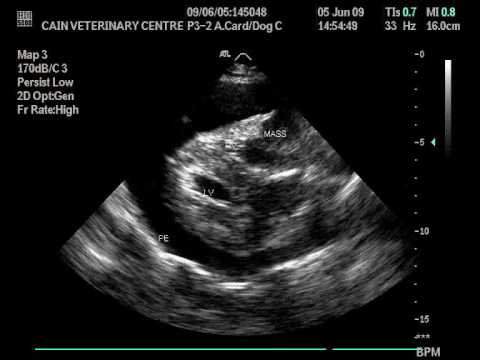

Haemangiosarcoma in the Right Atrium of a dog

MYXOMA TTE

Atrial Myxoma in Echocardiography || Dr. Shankar Dey